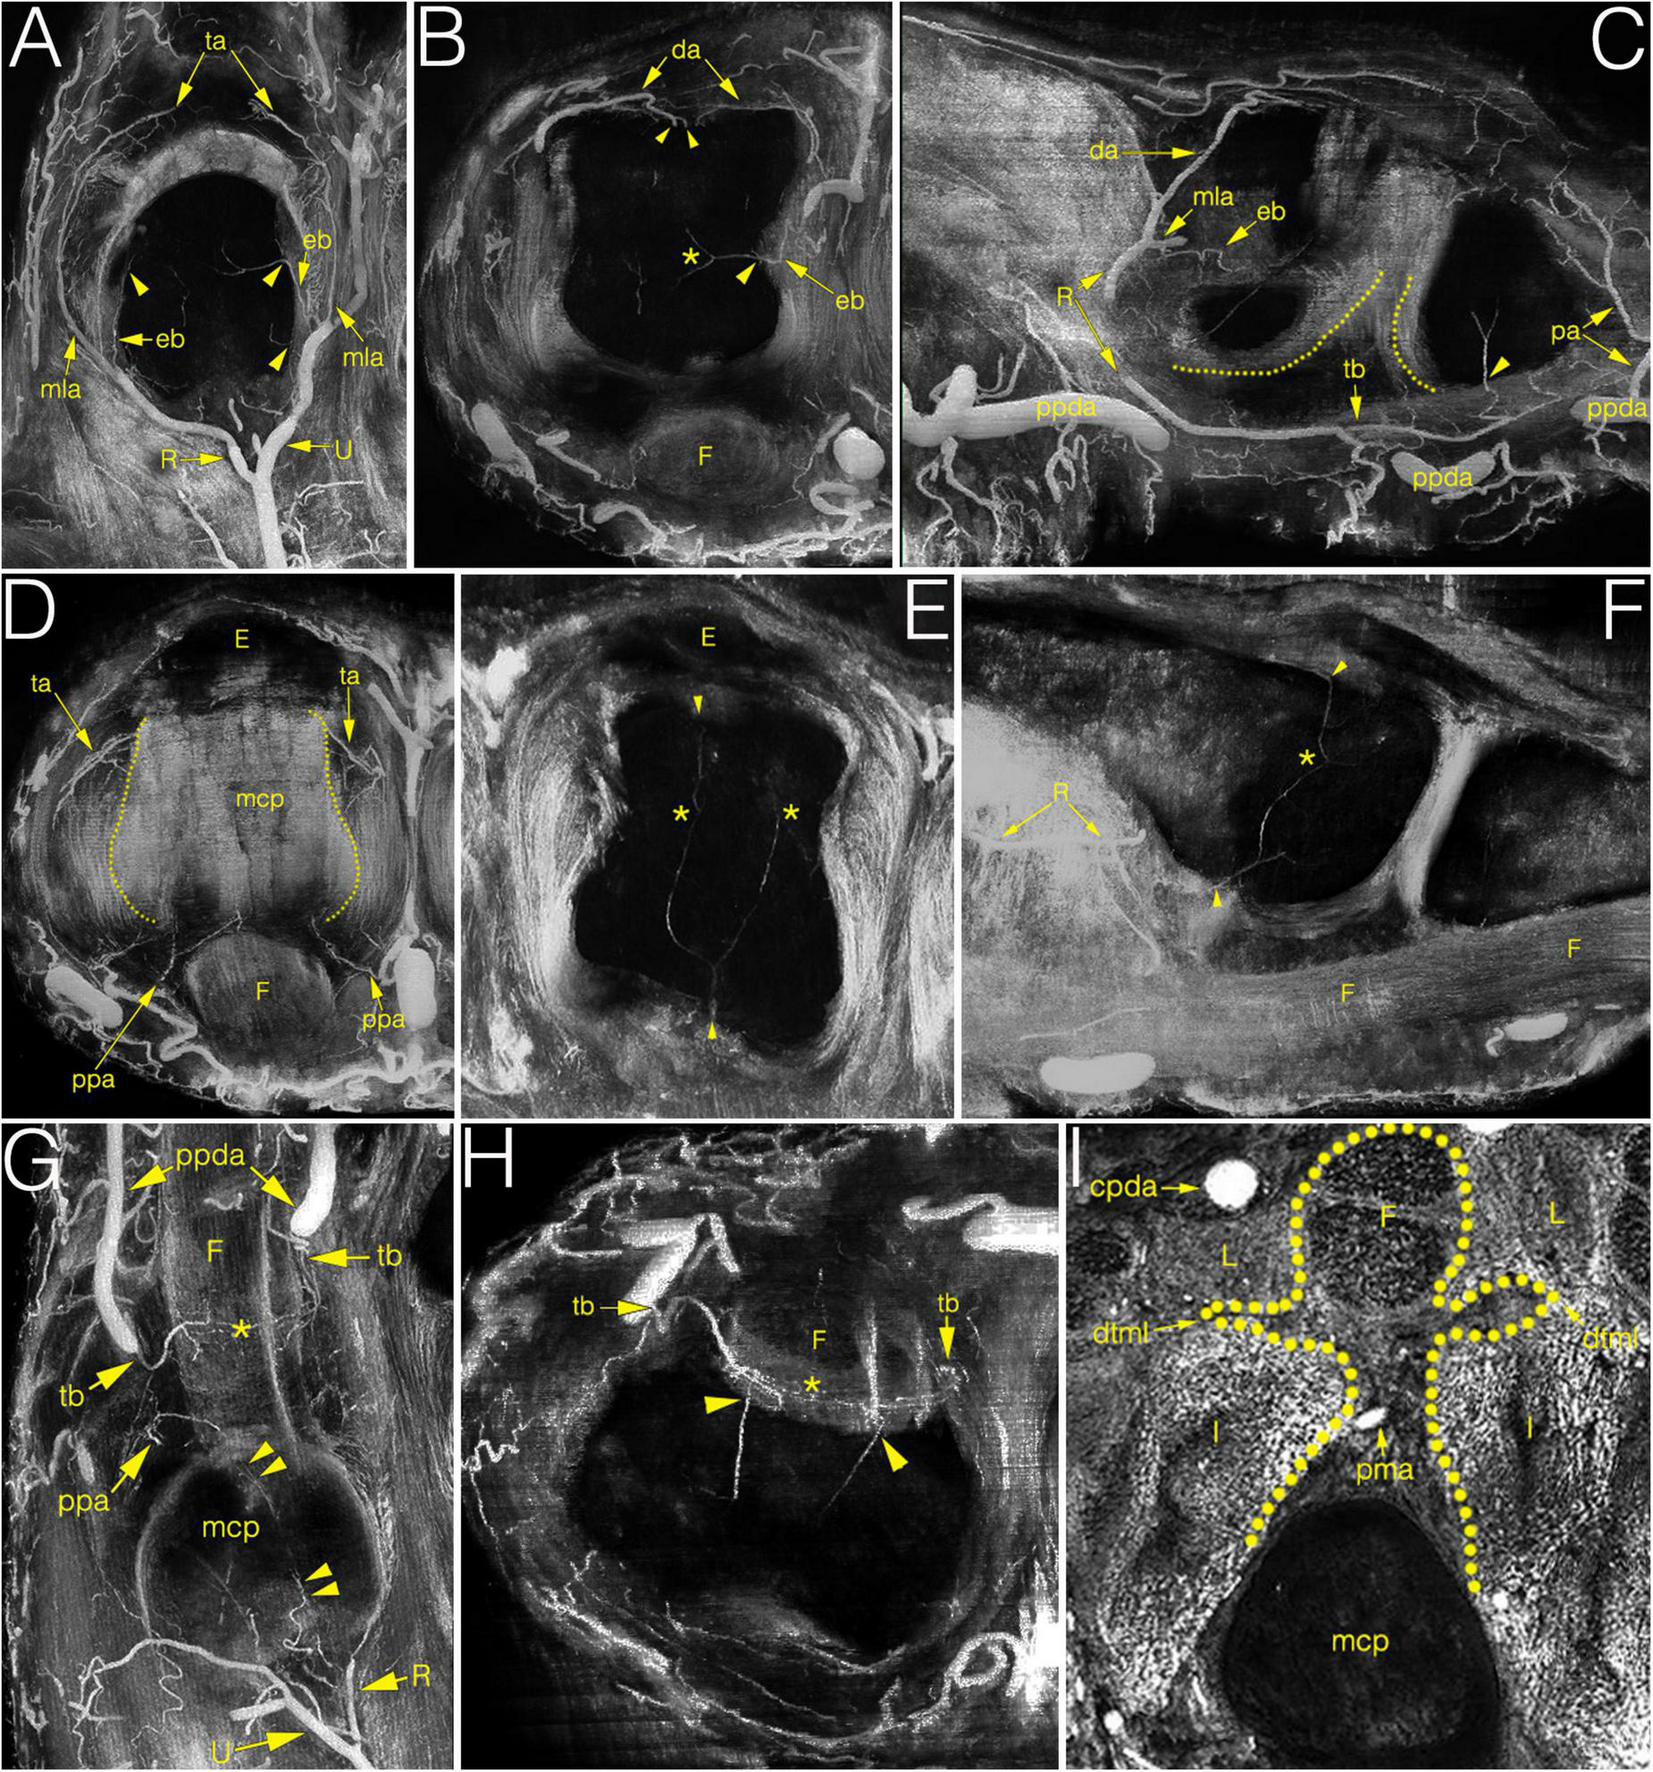

FIGURE 4

Multiplanar (MIP) image reconstructions on cryosectioned specimens demonstrating the relationship between arteries and joint structures. (A–C) main supplying branches on coronal, axial and sagittal plane, respectively. Note on C the elongated anastomosis between the R-branch and the tenosynovial branch. Dotted lines indicate the palmar articular surfaces of bones; (D) palmar plate artery and the triangular arcade on the axial plane. Dotted lines indicate the lateral borders of metacarpal head; (E,F) blood supply of the metacarpal head on the axial and sagittal plane. Note the anastomosis between the dorsal, palmar and lateral enosseal arteries, respectively. Compare with panel (B). (G,H) origin and course of the tenosynovial trunk on the coronal and axial plane. Note the anastomosis between the two sides within the flexor tendon. (I) homuncule shaped (dotted line) soft tissue complex in the center with the palmar metacarpal artery on the axial plane. *, anastomosis; cpda, common palmar digital artery; da, dorsal arcade; dtml, deep transverse metacarpal ligament; eb, enthesial branch; E, extensor tendon; F, flexor tendon; I, interosseous muscle; L, lumbrical muscle; mcp, metacarpal; mla, main lateral artery; pa, phalangeal arcade; pma, palmar metacarpal artery; ppa, palmar plate artery; ppda, proper palmar digital artery; R, R-branch; ta, triangular arcade; tb, tenosynovial trunk; U, U-branch; arrowheads, entry point of enosseal arteries; doubled arrowheads, supplying artery from the R-branch to the flexor tendons.